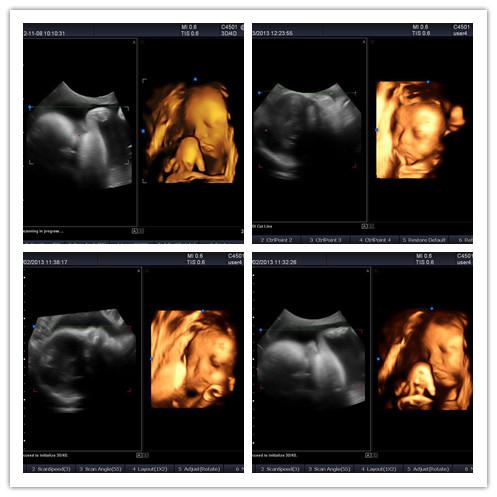

3、實(shí)時(shí)三維成像(4D) (選購(gòu))

通過(guò)SIUI自主研發(fā)的高質(zhì)量實(shí)時(shí)三維容積探頭,輕松實(shí)現(xiàn)實(shí)時(shí)三維成像,方便、快捷、實(shí)時(shí)地顯示胎兒或臟器的立體信息。